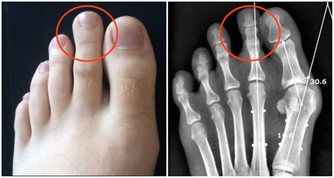

一: 手脫皮的治療: 1:韭菜汁治療手脫皮:取鮮韭菜一把, 洗凈搗爛成泥,用紗布包好,擰出其汁, 加入適量的紅白糖,每日服一次,一般連服四次可愈. 2:柏樹枝葉治指掌脫皮:用鮮柏樹枝葉加水煮沸。 浸泡患掌,堅持一個多月後,治癒。 3:黑雲豆煮食醫治手裂脫皮:將70克純黑雲豆用火煮爛 ,連湯帶豆食用,每日二次,食用五千克為一個療程。 一個療程後停食此方半個月, 共三個療程後即可治好手裂脫皮病症。 4:羊油治"皴":將涮羊肉湯上層的浮油冷卻後撈出, 放進小瓶內後。開水燙瓶子,使之熔化,再冷卻, 去掉沉在下面的水和雜質,反覆兩次,冬春備用。 用此油擦手、腳、臉部皮破患處可治癒。 一、手脫皮的治療 1、韭菜汁治療手脫皮:取鮮韭菜一把,洗凈搗爛成泥,用紗布包好,擰出其汁,加入適量的紅白糖,每日服一次,一般連服四次可愈。 2、柏樹枝葉治指掌脫皮:用鮮柏樹枝葉加水煮沸。浸泡患掌,堅持一個多月後,治癒。 3、黑雲豆煮食醫治手裂脫皮:將70克純黑雲豆用火煮爛,連湯帶豆食用,每日二次,食用五千克為一個療程。一個療程後停食此方半個月,共三個療程後即可治好手裂脫皮病症。 4、羊油治皴:將涮羊肉湯上層的浮油冷卻後撈出,放進小瓶內後。開水燙瓶子,使之熔化,再冷卻,去掉沉在下面的水和雜質,反覆兩次,冬春備用。用此油擦手、腳、臉部皮破患處可治癒。 二、足後跟痛的治療 5、新鮮蒼耳治足後跟痛有特效:具體做法是,將鮮蒼耳葉數片墊於襪內足跟處,24小時更換新葉一次,通常七次可愈。 6、石揉治足跟痛:用石頭蛋揉患處(石頭小雞蛋型)。開始先輕些逐漸加重,每天兩次,每次20分鐘,一個月時間痊癒。 7、治多年腳跟痛:針麻20克,湖腦50克(中藥店有售),針麻搗碎與湖腦合拌一起,分五份裝入縫製好的小布袋裡,每次1袋墊在腳跟痛點上,一周換一次,用四至五次即愈。 8、指甲草(又叫鳳仙花)根莖煮水治腳跟痛:找五六棵約30公分高的指甲草根莖(只用根兒),枯萎的最好,洗去泥土的,放入搪瓷或鋁製的洗腳盆里,加上可漫過腳的水煮開後,添一小勺鹽,稍微攪一攪就可以了。開始水太燙,可先用一個棉墊蓋上盆,腳伸進去熏一熏痛處,稍後就要反覆洗泡,直至水涼為止。第二天加點水煮開繼續洗。一天一次,連續五次,痛的感覺就漸漸消失了。 9、治大腳趾根部關節骨質增生:用醋兩大碗(以便沒過腳面),一兩干黃花菜放醋里,用慢火煎熬至黃花菜漲開,用來燙腳,兩三次就好。 10、巧治打嗝:制止打嗝的方法非常簡單,即分別用自己的左右手指指甲,用力掐住中指頂部,大約過1~2分鐘以後,即可達到制止打嗝的目的了。此外,也可能用指甲掐「內關穴」,此穴位於手腕內側6~7公分處,即第一橫紋下約2橫指的距離,其止打嗝的效果也比校好。 三、手腳抽筋的治療 11、巧治手腳抽筋:手或者腳抽筋了,只要你立即用拇指和食指掐住嘴唇的人中穴,持續用力掐20-30秒鐘後,抽筋的肌肉即可鬆弛,痛疼也隨之消除,用此法對付手指或腳抽筋,有效率可達95%以上。 四、腳雞眼的治療 12、貼豆腐治腳雞眼:睡覺前將患處用溫水洗凈,把市售豆腐切成片貼在患處,用塑料袋裹好,外套襪子固定。次日起床後、去掉豆腐,用溫水洗腳。 13、鹽水治雞眼:用一湯匙食鹽加生水煮沸,或用開水化開,待稍涼後燙腳,燙後擦乾即成,不要用清水洗。每天燙腳兩次,約一周左右,雞眼自然脫落,至今已十多年未再犯。 14、芹菜葉治雞眼:具體做法、芹萊葉洗凈,將水甩掉,捏成一小把,在雞眼處塗擦,至葉汁擦乾時為止。每日3一4次,僅用一周雞眼即被吸收,患腳完好如初。 15、大蒜治雞眼:方法是把大蒜砸成泥,攤在布上備用,把腳洗凈,沿雞眼周圍用針挑破,以見血絲為宜,然後把攤在布上的蒜泥貼到患處包好。照此法換三次,雞眼完全消失了,至今未犯。 16、洋蔥頭治雞眼:用洋蔥頭擦,擦一個多星期,雞眼果真不見了。 17、蔥白治雞眼(腳上長雞眼):用熱水泡腳後,剪了一塊比雞眼稍大點的蔥白貼在患處,用傷濕止疼膏固定。 18、吃醋蛋治雞眼:雞蛋3隻,醋適量。將雞蛋泡進醋里,密封7天,然後撈出煮熟吃,一般5一6天後,雞眼裡即生長出嫩肉,把患處逐漸頂高。這時每天臨睡前用熱水將患處泡軟,再用刀颳去硬皮,持續7一8天,雞眼即可全部脫落。 19、煤油治雞眼:用熱開水泡一會兒,用刀將雞眼老皮削去,點上一滴煤油就好了。經實踐,治癒率達百分之百。 20、腳雞眼、刺猴:用大麻子1粒,搗爛抹上用膠布貼上,一次即愈。 21、雞眼、侯子:先將患處外部老皮消去,再塗上清涼油,用香菸火燻烤,至疼時稍堅持後拿掉煙火,一日二次,5天可脫落不發。 五、手腳皸裂的治療 22、黃蠟油治手腳裂:治癒。其法、香油100g、黃蠟(中藥店可買到)20至30g,用火將香油熱熬放黃蠟,待黃蠟熔化即成。用法、先用溫熱水泡洗手(腳)部10至15分鐘,待手(腳)泡透擦乾,擦蠟油於患處,用火烤乾當時就有舒適感,每日兩次,一周即愈。 23、麥秸根治手腳乾裂:取麥秸切成十公分長的小段,清晨取一把,用清水浸泡一天,晚上在火上煮約十分鐘後浸泡手或腳,三天換一次水和麥秸,一周見效。 24、保濕霜治腳跟乾裂:腳跟部位粗糙乾裂,用保濕霜,每晚燙洗腳後跟即在腳後跟裂周圍均勻塗抹,六七天後奇蹟般的好了. 25、灌油根治腳裂:使用獾油只半個多月的時間,裂腳就光滑了,獾油可根治腳裂。 26、橘皮可治手足乾裂:桔子皮二三個或更多,放入鍋或盆里加水煎二至五分鐘後,先洗手再泡腳至水不熱為止,每天最少要洗一次,連洗多天,就有明顯的效果。 27、芥末治腳裂口:方法是、用40C左右的溫水洗腳,泡10分鐘左右,然後擦乾;用溫水調好芥末,漿糊狀,不要太稀,用手抹在患處;穿上襪子,以保清潔;第二天再用溫水洗腳,再抹,2一3次即愈。 28、醋治療腳裂口:一斤醋,放在鐵鍋里煮,開鍋後五分鐘,把醋倒在盆里,待溫後把手腳泡在醋里10分鐘,每天泡兩三次,7天一療程。兩個療程後就徹底好了。 29、治療腳裂一法:用熱水泡一下腳,然後拿酒精消毒過的刀片,將腳跟的硬皮和干皮一層層削掉,一直到露出軟皮部分為止,將凡士林油紗布裹在腳跟上,再用繃帶固定好。隔3天換2次油紗布,一周後就徹底治癒了。 30、剩茶水可治手足裂:將白天喝過的剩茶水,在睡覺前對些熱水泡洗手足約十分鐘,堅持了一周後,手足皮膚漸漸光滑了,裂口也漸漸癒合,效果很明顯。 31、維生素E可治手腳乾裂:方法是、把維生素E丸,用針扎一個眼,把油擠患處塗抹(一個丸可用多次),每次洗過手抹,癒合後也要常抹,不再犯。 32、用蜂蜜揉搓可治手皸裂:每日早飯後,雙手洗凈擦乾,將蜂蜜塗於手心手背指甲縫,